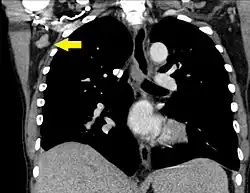

- By size, where lymphadenopathy in adults is often defined as a short axis of one or more lymph nodes is greater than 10mm.[29][30] However, there is regional variation as detailed in this table:

| Mediastinum | |

| Mediastinum, generally | 10 mm[31] |

| Superior mediastinum and high paratracheal | 7mm[34] |

| Low paratracheal and subcarinal | 11 mm[34] |